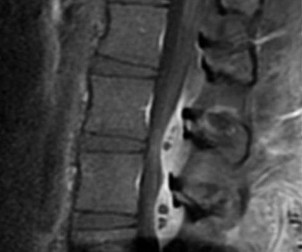

Question 6:

A 45-year-old manual laborer presents with chronic radial-sided wrist pain, recalling a fall on an outstretched hand 5 years ago. Imaging shows a scaphoid nonunion with radioscaphoid and capitolunate arthritis, but the radiolunate joint remains completely preserved. This describes which stage of Scaphoid Nonunion Advanced Collapse (SNAC), and what is a standard surgical option?

Correct Answer: SNAC Stage 3; Four-corner fusion with scaphoid excision

Explanation:

The progression of SNAC wrist is predictable. Stage 1 involves arthritis at the radial styloid; Stage 2 involves the entire radioscaphoid joint; Stage 3 involves the capitolunate joint; Stage 4 involves the radiolunate and/or entire carpus. Because the radiolunate joint is preserved in Stage 3, a four-corner fusion (capitate, hamate, lunate, triquetrum) with scaphoid excision is the standard salvage procedure. Proximal row carpectomy is contraindicated due to capitolunate arthritis.